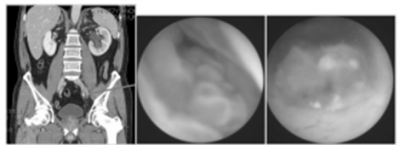

예시 1) 58세 남성, Rt. flank pain 및 UA상 hematuria로 응급실 내원

사진설명: nonenhanced CT에서 Rt. hydronephrosis및 proximal ureter stone이 보임.

환자는 진통제 투여 후 통증이 호전되어 외래에서 추적관찰을 하기로 함.

사진설명: 2주 후 nonenhanced CT에서 Rt. hydronephrosis 소실 소견이 보이지만 Rt. mid-ureter에 stone이 지속되고 있음.

진단 및 치료적 ureteroscopy을 시행하기로 함.

좌측 사진은 상기 환자의 Rt. ureteral orifice에 urothelial neoplasm이 있는 사진이고 우측 사진은 이를 제거하고 ureteroscopy를 시행하였을 때 보이는 ureter내 urothelial neoplasm의 모습이다.